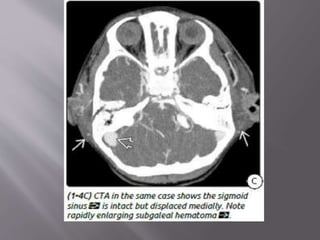

b) Venous EDH- smaller, low pressure, develop

slowly

Most venous EDHs are caused by a skull fracture

that crosses a dural venous sinus and therefore

occur in the posterior fossa near the skull base

(transverse/sigmoid sinus) or the vertex of the

brain (superior sagittal sinus).